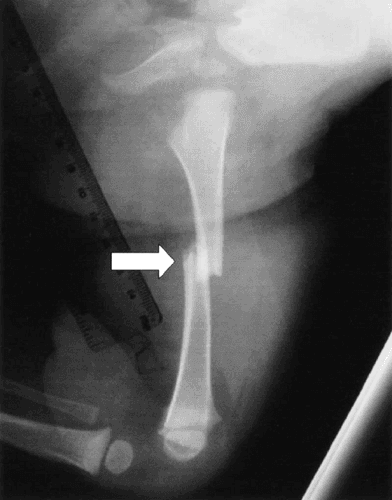

Spiral Fracture - हाडाच्या एखाद्या भागाला पीळ पडणे.